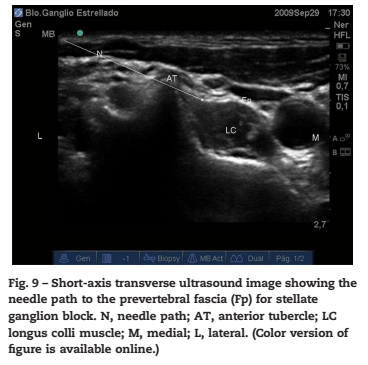

구체적으로는,

경추 7번(C7) 횡돌기 하단에서

첫 번째 늑골의 상단에 걸쳐 위치하는데요.

척추동맥의 안쪽 또는 뒤쪽에 자리 잡고 있으며,

폐 첨부(cupula pleurae)와 매우 가깝습니다

하경부 신경절과 첫 번째 흉부 신경절이 합쳐지고

교감신경 줄기는 경장근(longus colli muscle) 위,

그리고 식도와 혈관을 감싸는

척추 앞 근막 (prevertebral fascia)

뒤쪽에 위치합니다.

3. 정확한 타겟팅:

바늘이 경추 6번 뼈의 돌기를 스치듯

안전하게 진입하여,

경장근(longus colli muscle) 앞쪽,

식도와 혈관들을 감싸는 근막 바로 뒤쪽 공간에

정확히 도달합니다.

이곳이 바로 성상신경절에 약물이

가장 잘 퍼져나갈 수 있는 핵심 공간입니다.